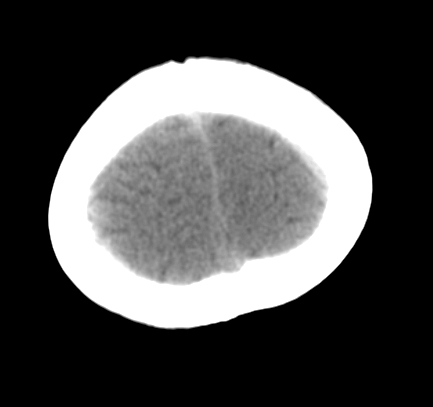

女,3岁,头部外伤一小时。半卵圆中心低密度是什么意思,病灶?侧脑室?请指教。

正常表现

幼儿正常脑白质表现,长期观察,必要时mr

从层面看不是侧脑室,考虑低密度变,建议mri。

不是侧脑室,考虑正常脑白质。为慎重,建议mr!